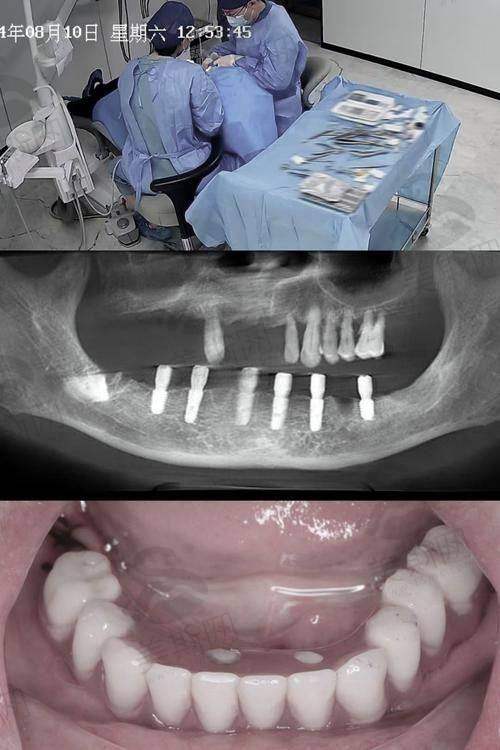

1. 牙齿种植:开展即刻种植、全口/半口种植修复、骨增量技术等,采用韩国登腾、瑞士ITI等国内外有名种植体品牌,结合3D导板精细种植技术,实现“当天种牙当天用”。

武威市新怡然口腔医院的核心特色技术为数字化精细种植技术,该技术通过“三维重建 - 导板设计 - 精细植入”三步流程,实现种植手术全程可视化、微创化。医院引进德国西门子Sirona CBCT设备,可严谨扫描牙槽骨密度、高度及神经走向,误差控制在0.1mm以内;采用3D打印技术定制种植导板,确保种植体植入角度、深度与术前规划完全一致,手术时间较传统方式缩短60%,创伤面积减少70%,术后肿胀率低于5%。此外,医院在隐形矫正领域创举“双膜联合矫正技术”,通过动态矫治膜与静态保持膜交替使用,将矫正周期平均缩短3 - 6个月,且复发性降低至1%以下。该技术已申请国内实用新型专项,目前累计完成种植病例2000余例、矫正病例3500余例,患者满意度达96.8%。

患者王先生(种植牙):“因为牙周病掉了两颗后牙,吃东西特别不方便。在新怡然做了即刻种植,李主事亲自手术,打了麻药几乎不疼,全程不到1小时就种好了。当天就能用临时牙吃饭,3个月后换了恒久牙冠,现在咬东西和真牙没区别。更让我满意的是价格透明,一开始就告诉我所有费用,没有额外收费,比我询问的其他医院便宜了2000多。医院还定期打电话回访,感觉特别负职责。”